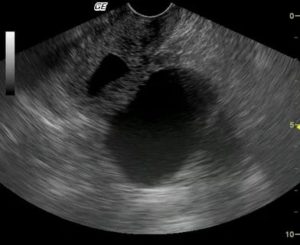

Чтобы выявить скопление жидкости, обязательно ультразвуковое обследование. Только оно способно точно определить серозометру.

Что делать, для обнаружения патологии? Существует ряд заболеваний, которые по своей симптоматике очень похожи между собой. Для выявления серозометры используются такие методы диагностики, как УЗИ и гинекологический осмотр.

Развитие серозометры возможно при наступлении менопаузы уже после 45 лет, но в большинстве случаев патология выявляется в постменопаузу у пациенток старше 60 лет. Болезнь в этом возрасте диагностируется у 40% женщин. Серозная жидкость может скапливаться не только в самой матке, но и в цервикальном канале.

Патология в этом случае обозначается термином серозоцервикс, это более тяжелое по сравнению с серозометрой состояние.